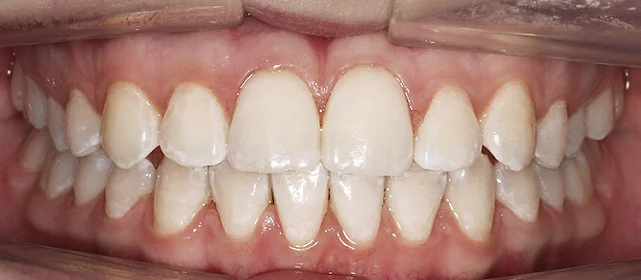

Нарушение соотношения челюстей и неправильное положение зубов — зубные ряды смыкались некорректно, зубы стояли со смещением.

Проблема: Пациентку не устраивало положение зубов и то, как смыкаются челюсти. Зубы стояли неровно, ряды сходились неправильно.